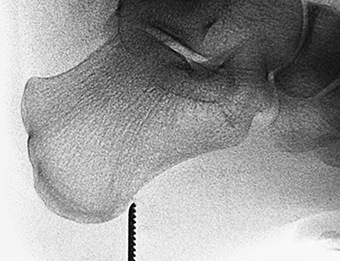

La apariencia anatómica es variable y se han clasificado en espolones sencillos e irregulares. El espolón sencillo es una estructura triangular que termina con una punta afilada, con una cortical ligeramente esclerótica y trabéculas bien desarrolladas. En contraste, los espolones irregulares tienen los bordes mal definidos y la trabeculación es poco clara y se producen cuando hay un fuerte proceso inflamatorio [52] (Figura 3).

Figura 3A

Figura 3B

Figura 3C

Figura 3. A, B, C) Imagen radiográfica de espolones del calcáneo.